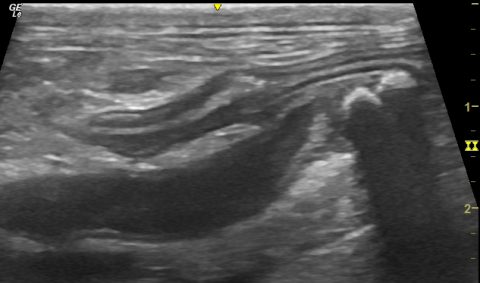

Sonography of presumed granulomatous colitis in a French Bulldog

A severe colitis refractory to conventional treatments is not uncommon in young French Bulldogs and Boxers in the UK: https://onlinelibrary.wiley.com/doi/pdf/10.1111/jvim.12020 A definitive diagnosis requires histopathology; conventionally using mucosal biopsies acquired at colonocopy. However, it’s certainly worth having a look with ultrasound before embarking on scoping. This helps to identify the worst-affected sections of … Continue reading